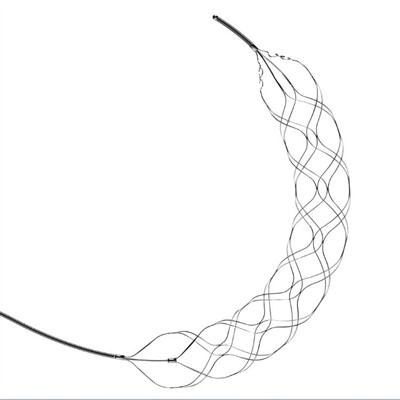

Trombektomijas stenta retrīvera priekšrocībasPēdējos gados trombektomijas stenta retrīveri ir kļuvuši par ļoti efektīvu ārstēšanas iespēju pacientiem, kuri cieš no akūta išēmiska insulta. Šī minimāli invazīvā procedūra ietver stenta retrīvera ie